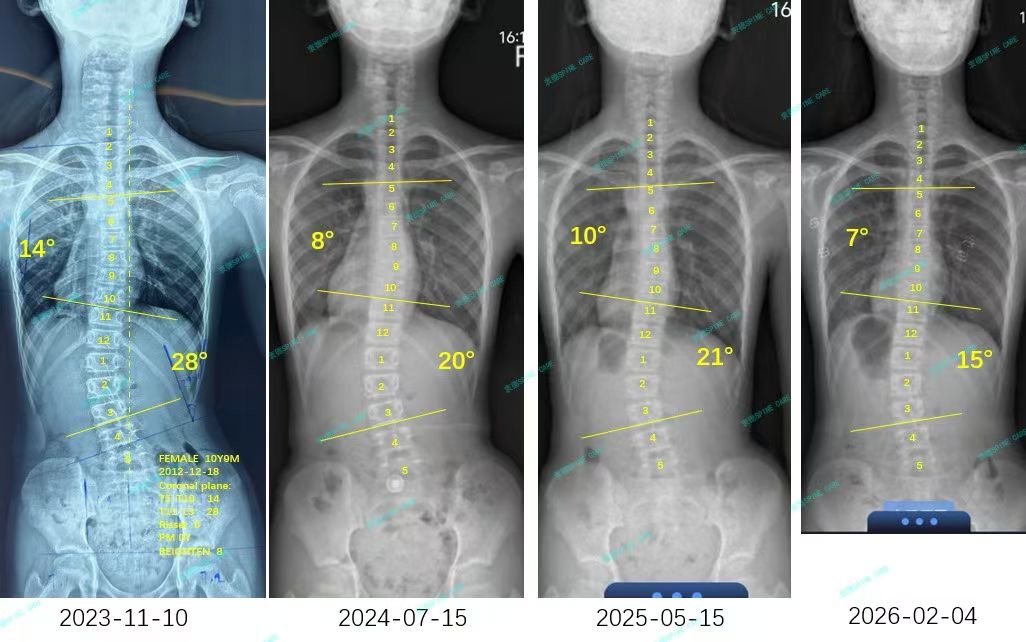

来自家长对衷德的评价(甜甜妈妈)